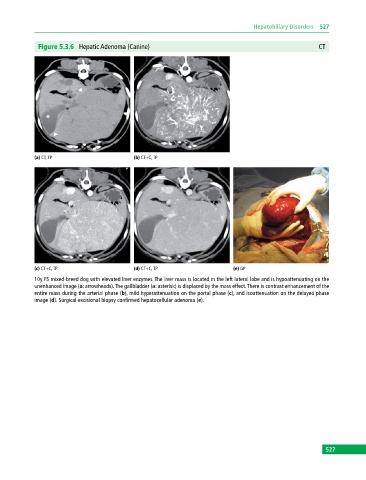

Figure 5.3.6 Hepatic Adenoma (Canine) CT

(a) CT, TP (b) CT+C, TP

(c) CT+C, TP (d) CT+C, TP (e) GP

10y FS mixed‐breed dog with elevated liver enzymes. The liver mass is located in the left lateral lobe and is hypoattenuating on the

unenhanced image (a: arrowheads). The gallbladder (a: asterisk) is displaced by the mass effect. There is contrast enhancement of the

entire mass during the arterial phase (b), mild hyperattenuation on the portal phase (c), and isoattenuation on the delayed phase

image (d). Surgical excisional biopsy confirmed hepatocellular adenoma (e).